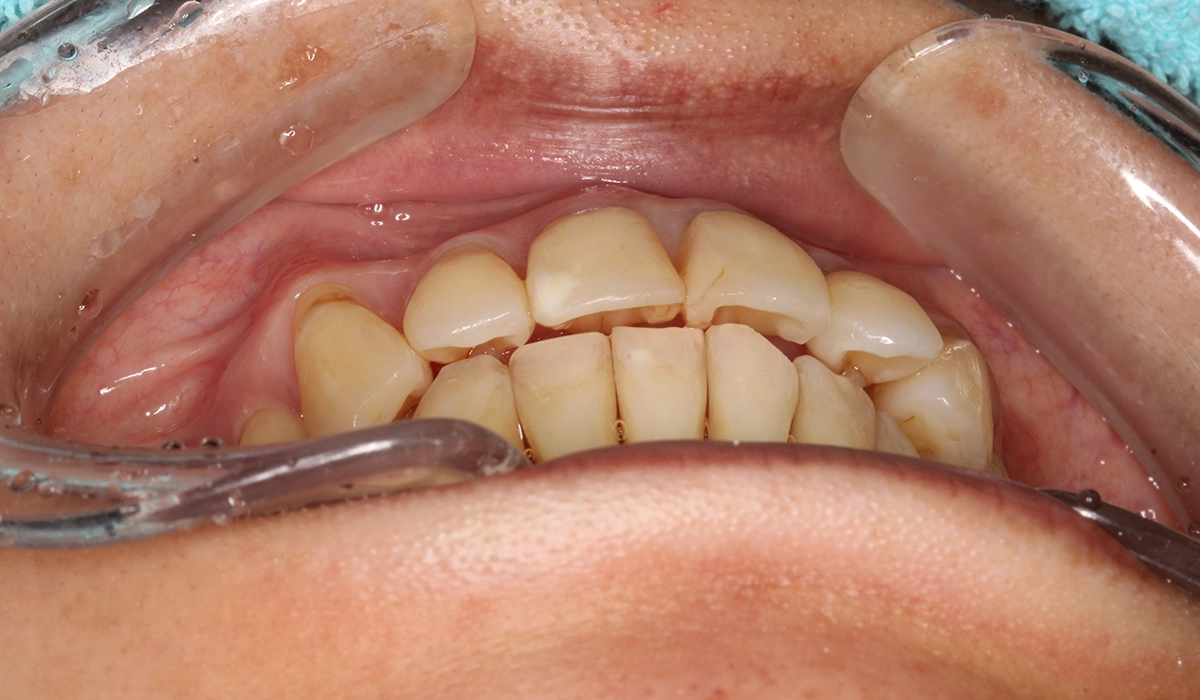

術後:前歯部

術後:オーバージェット